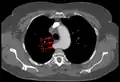

-

Aberrant subclavian artery at axial CT-scan. (1) trachea, (2) esophagus, (3) aberrant subclavian artery. -